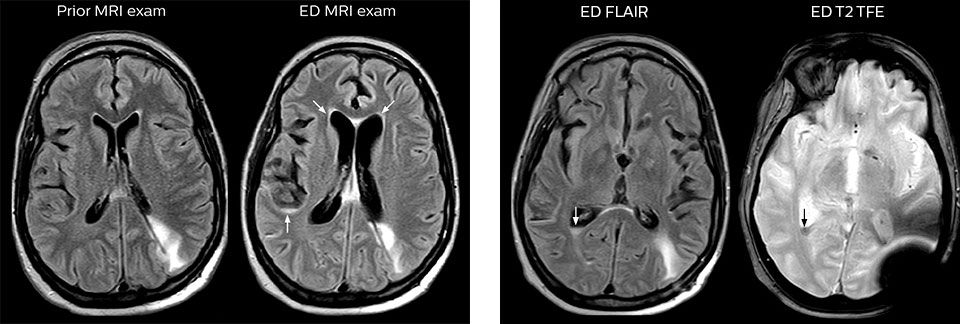

“Avant, nous réalisions des examens TDM en raison de leur disponibilité et de leur rapidité”, admet le Dr Karis, “mais si une IRM pouvait être aussi efficace qu’une TDM, les médecins traitants préféreraient probablement, dans certains cas, l’IRM à la TDM. Réduire le nombre d’examens TDM chez les patients de moins de 40 ans ne présentant aucun signe de trouble grave, comme un AVC, était également une des principales raisons justifiant l’introduction de l’IRM dans le service d’urgences. “L’IRM est un examen plus efficace pour identifier les lésions des tissus mous dans le cerveau. Ce qui a vraiment influencé la décision d’un point de vue administratif, c’est la dose de rayonnement totale à laquelle sont exposés les patients du service d’urgences, et la possibilité de la réduire en y introduisant l’IRM.”

Pour minimiser la durée des acquisitions, des protocoles d’examen IRM rapides (ExamCards) ont été mis au point. Ils réduisent la durée d’acquisition totale à moins de 10 minutes pour certains examens. Des techniques comme le mDIXON (DIXON modifié) sont utilisées pour une acquisition solide des images d’IRM sans graisse dans l’environnement stressant des urgences.

“Nous utilisons beaucoup le mDIXON TSE dans notre imagerie du rachis en service d’urgences”, déclare le Dr Karis. “Ce qui est particulièrement appréciable, c’est sa fiabilité par rapport au type de susceptibilité des problèmes pouvant survenir avec des images spectrales classiques saturées en graisse ; ces problèmes sont essentiellement éliminés grâce à la technique mDIXON. C’est vraiment un avantage de disposer de l’imagerie sans graisse nécessaire à la technique mDIXON dans notre service d’urgences.”

“Pour les examens de routine sans contraste du rachis cervical et thoracique, par exemple, nous réalisons une séquence mDIXON T2 TSE qui produit deux sorties : les images pondérées en T2 avec graisse et eau, et les images sagittales pondérées en T2 avec eau uniquement. Ensuite, nous réalisons également un examen échographique du gradient axial.”